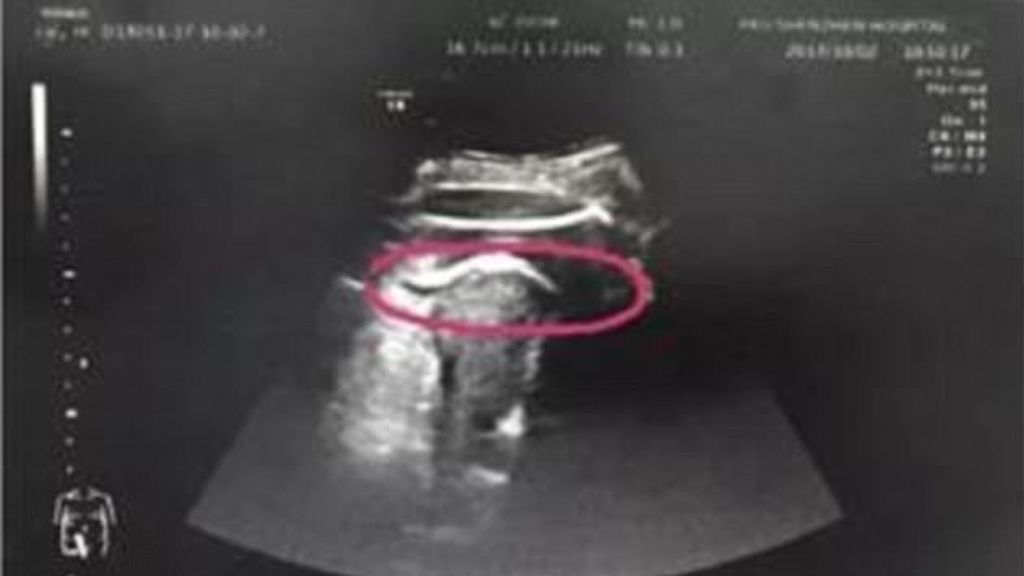

Una mujer llegó en estado grave al Hospital de Shenzhen de la Universidad de Pekín después de que su bebé de 35 semanas le diese una patada en el vientre y le perforase el útero.